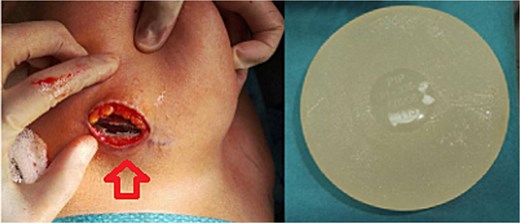

The patient underwent bilateral implant removal 2 weeks later.

Intraoperative findings:

A partial capsulectomy was performed on the left side due to poor dissection planes. Histopathology revealed benign features.